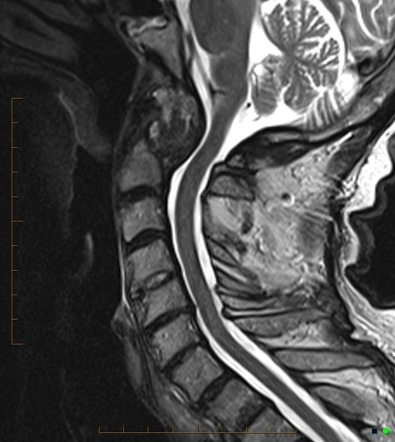

chiari malformation

I: downward displacement of cerebellar tonsils, often associated with syringomyelia

II: downward displacement of medulla, 4th ventricle and cerebellum through foramen magnum, often associated with myelomeningocele